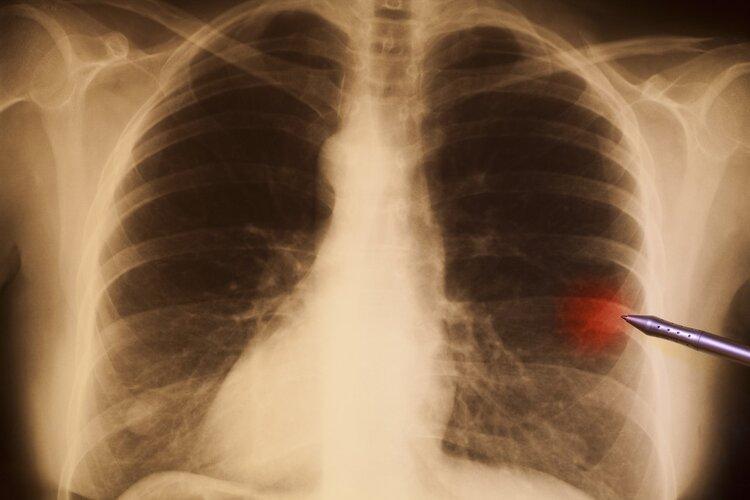

1、肺結節樣鈣竈化

上海市肺科醫院呼吸內科副主任醫師胡洋介紹:如果報告單上顯示鈣化結節、肺結節樣鈣化竈等字樣,都無需處理,這些多數疾病恢復後的疤痕,不會影響肺功能。